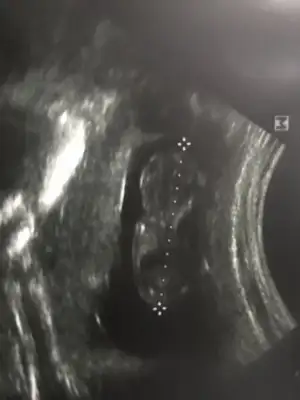

ay resmen gobegim cikmisssss

ay resmen gobegim cikmisssss

ahhahaha inanamiorummmm hiç kilo almadım hatta 5 kilo verdim zayiftim daha da zayıfladım ama kocaman minnoş bı göbeğim var yaaa.Allahim bu duyguyu yaşamak isteyen herkese nasip etsin.Bize de sagsalim zamanında kucağımıza almayı nasip etsin

ahhahaha inanamiorummmm hiç kilo almadım hatta 5 kilo verdim zayiftim daha da zayıfladım ama kocaman minnoş bı göbeğim var yaaa.Allahim bu duyguyu yaşamak isteyen herkese nasip etsin.Bize de sagsalim zamanında kucağımıza almayı nasip etsin